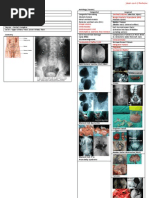

Obstructive Uropathy Overview and Management

1. Obstructive uropathy occurs when urine flow is obstructed, causing stasis, dilatation, and infection which can lead to renal failure if not diagnosed early. 2. Posterior urethral valve is the most common cause of severe subvesical obstruction in male infants, appearing as mucosal folds in the posterior urethra. 3. Treatment involves establishing bladder drainage, correcting fluid and electrolyte imbalances, and definitive surgery to excise the valve, with long-term follow-up due to risks of complications like chronic renal failure.

Chapter 14 OBSTRUCTIVE UROPATHY Introduction Normally, urine flow occurs in a stream & without effort.

. Obstruction results into stasis, dilatation and infection. If it is not diagnosed early, renal failure ensues. Obstruction manifests as i. dribbling ii. straining iii. dysuria iv. reflux of urine v. Distended bladder Urinary ascites

vi.Hydronephrosis in long standing cases resulting into renal impairment, failure to thrive, anorexia & vomiting. Note, Lower tract urinary tract obstruction is the most common cause of neonatal ascites which is due to rupture of dilated pelvis with extravsation of urine.

POSTERIOR URETHRAL VALVE Introduction It is the most common cause of severe subvesical

obstruction in the male infant. (Note, females do not have posterior urethra) Valves appear as mucosal folds in the posterior urethra Early obstruction during renal development may result in renal dysplasia Clinical Presentation i. Dribbling ii. Poor urinary streams in neonates & infants iii. Bladder All these form triads iv. Symptoms of uraemia v. Symptoms of infection

Complications The more severe the obstruction, the more the degree of complications. Later, in infancy i. Vomiting ii. Failure to thrive secondary to chronic renal failure iii. Dehydration secondary to diabetes insipidus Older children i. Enuresis may be the presenting complaint. Diagnosis o Can be made prenatally by ultrasound which reveals an

enlarged bladder & hydronephrosis. Investigation 1. Micturating Cystourethrogram is diagnostic. It shows o Dilated elongated posterior urethral valve o Trabeculated baldder o There may be urinoma or urinary ascites 2. Intravenous Urogram It is not routinely done. It may show extensive hydronephrosis and hydroureters. 3. Sepsis screen

Treatment

Immediate i. Fluid & Electrolyte correction i.e o Metabolic acidosis o Sodium Depletion o Dehydration ii. Establish bladder drainage by urethral (preferred) or suprapubic catheterization or vesicostomy(definitive treatment). In very ill patient, do urinary diversion by bilateral, ureterostomy. It is rarely done nowadays. iii. Give antibiotics

Definitive o Is surgery i.e excision of the valve o In the past, obliteration with diathermy used to be done. But, recently, what is done is Mohans valvotomy. Follow up o Is done because of the complications, to monitor for continence, stricture or development of chronic renal failure Prognosis o Depends on the severity of renal damage and

dysplasia at the time of diagnosis. Those who present late have poorer prognosis.